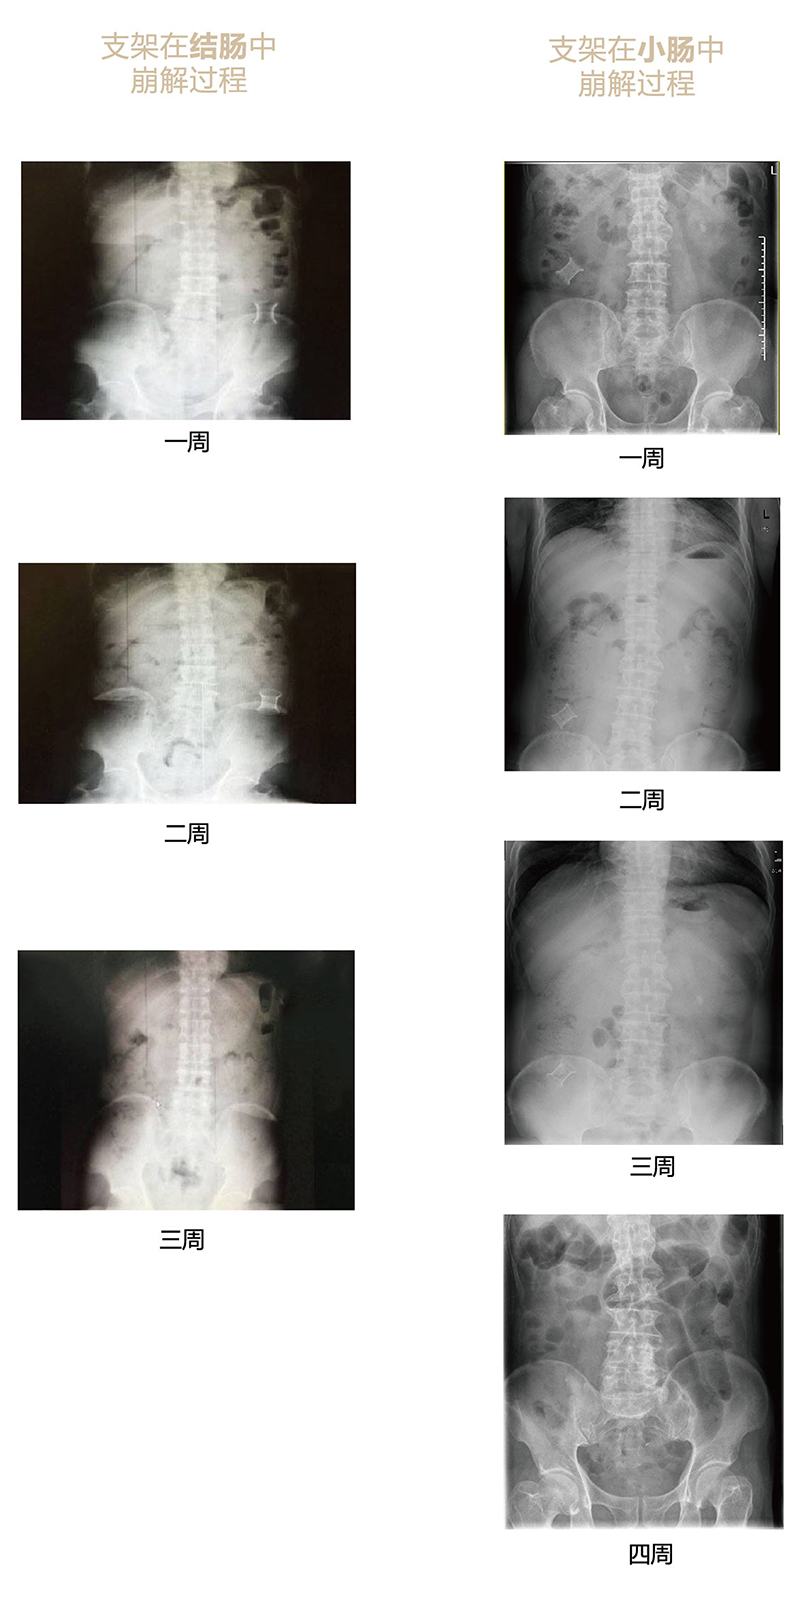

“可崩解腸道吻合器”由聚乙醇酸(PGA)與硫酸鋇按重量比7:1混合注塑制成,在X線下顯影,可動(dòng)態(tài)追蹤可崩解腸道吻合器(支架)在腸道內(nèi)崩解過(guò)程。

為解決該問(wèn)題,蔡秀軍教授在“支架法空腔臟器吻合技術(shù)”的理念基礎(chǔ)上,又發(fā)明了“蔡氏腸轉(zhuǎn)流術(shù)”,這是一種應(yīng)用“可崩解腸道吻合器HB型(可崩解腸轉(zhuǎn)流支架)”(發(fā)明專利號(hào):201910794214.3),的支架法腸道轉(zhuǎn)流術(shù),此創(chuàng)新術(shù)式既能保護(hù)低位吻合口,更避免了回納術(shù)??杀澜饽c轉(zhuǎn)流支架在直腸癌根治術(shù)中植入遠(yuǎn)端回腸,可確保完全阻斷腸腔,用腸造瘺管在轉(zhuǎn)流支架近端行腸造瘺,起到完全轉(zhuǎn)流的作用。腸轉(zhuǎn)流支架在二至三周內(nèi)逐漸崩解,并在四周內(nèi)完全排出體外,恢復(fù)腸道通暢后拔除造瘺管,避免了傳統(tǒng)造口回納的二次手術(shù)。該創(chuàng)新術(shù)式具有方法簡(jiǎn)單、吻合時(shí)間短、人體內(nèi)無(wú)異物永久殘留、不破壞吻合口粘膜下血管,并能預(yù)防吻合口漏、可避免人工肛門留置及二次手術(shù)、治療周期可縮短至二至四周、患者生理心理創(chuàng)傷顯著減少。